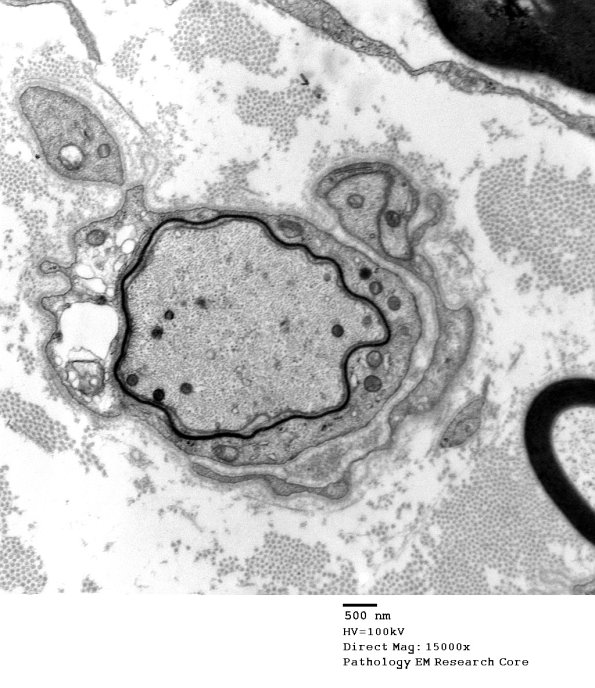

Multiple examples of naked and remyelinating axons. (electron micrographs)